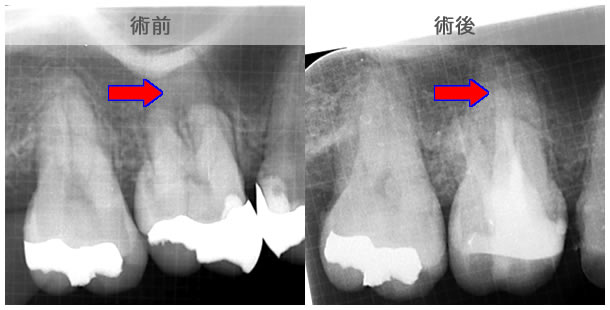

原因は赤の矢印が指す、根の周りの病巣でした。

治療後は青い矢印が指す場所には、黒い病巣が消失しています。

| 治療説明 | 自覚症状で歯が浮いた感じがしていました。上顎大臼歯・頬側根の根尖部にX線透過像の病巣があります。根充剤を除去・拡大清掃・根管充填を行いました。根尖から根充剤がはみ出ていますが、根尖部のX線透過像は見られなくなりました。そこ後、自覚症状もなくなりました。 |

|---|---|

| 治療期間 | 6〜24ヶ月 |

| 治療費用 | 150,000〜300,000円 |

| 治療に伴うリスク | 根管内からの治療で根尖病巣が治らない場合は、外科的に根尖病巣を除去する必要があります。 再根管治療を繰り返す場合、歯根の厚みが薄くなり、歯根破折のリスクが高まります。 |